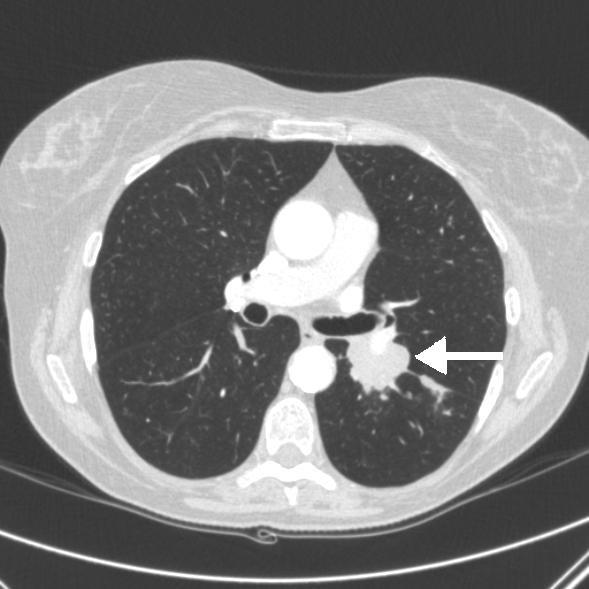

A 64-year-old British Caucasian woman presented to our hospital with a 12-week history of confusion and short-term memory loss. She was hyponatremic with a serum sodium level of 128mmol/L. Moreover, there was evidence of left hilar prominence on the chest radiograph. A thoracic computed tomography scan showed left hilar opacity with confluent lymphadenopathy. A percutaneous biopsy confirmed a diagnosis of small cell lung cancer. There was no radiological evidence of brain metastasis on the computed tomography scan. In view of continued cognitive impairment, which was felt to be disproportionate to hyponatremia, a magnetic resonance imaging scan of the brain was undertaken. It showed hyperintense signals from both hippocampi, highly suggestive of limbic encephalitis presenting as a paraneoplastic manifestation of small cell lung cancer. She had a significant radiological and clinical response following chemotherapy and radiotherapy.

一名64岁的英国白种女性因12周的意识模糊和短期记忆丧失前来我院就诊。她低钠血症,血清钠水平为128mmol/L。此外,胸部X线片显示左肺门突出。胸部计算机断层扫描显示左肺门模糊,伴有融合性淋巴结病。经皮活检确诊为小细胞肺癌。计算机断层扫描未发现脑转移的影像学证据。鉴于持续存在的认知障碍,且认为与低钠血症不成比例,遂对脑部进行了磁共振成像扫描。扫描显示双侧海马呈高信号,高度提示边缘叶脑炎,为小细胞肺癌的副肿瘤表现。化疗和放疗后,她在影像学和临床上均有显著改善。